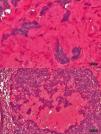

Carcinoma de células basales con patrón cilindromatoso. Detalle de un nido neoplásico constituido por células basaloides que conforman empalizadas periféricas rodeadas de artefacto de retracción. En el seno tumoral se observa gran cantidad de material amorfo, hialino tipo membrana basal (H&E ×100).

Varón de 91 años de edad, con fenotipo cutáneo II, que consultó en el servicio de dermatología por la presencia de una pápula eritematosa no ulcerada en la mejilla izquierda de 4 meses de evolución, y que medía 1cm de diámetro máximo. Con el juicio clínico de carcinoma basocelular, se decidió realizar la exéresis lesional. El estudio histológico demostró una epidermis sumamente adelgazada, monoestratificada, focalmente presionada por la presencia, a nivel dérmico, de numerosos nódulos geográficos basaloides que se extendían en profundidad hasta la unión dermo-hipodérmica (0,5cm) (fig. 1). Los nidos geográficos proliferantes se unían en superficie con el estrato basal epidérmico, del que parecían originarse. Las células lesionales mostraban atipia leve-moderada, y se disponían constituyendo empalizadas en la periferia de los nódulos, estando estos rodeados de artefacto de retracción (fig. 2). Mientras que algunos nódulos basaloides mostraban cambios quísticos en su seno, llamaba poderosamente la atención la presencia de un patrón cilindromatoso en otros. Este último patrón estaba definido por la presencia de un estroma intensamente colagenizado e hialinizado en torno a los nódulos tumorales, con presencia de prolongaciones hialinas hacia el centro de los mismos, formando auténticos cilindros a nivel terminal, y dando lugar a una imagen similar a aquella característica de los cilindromas (fig. 3). Con la aplicación de técnicas del PAS-azul alcián, se tiñeron las estructuras cilindromatosas de un tono magenta, mientras las estructuras quísticas se tiñeron de azul, demostrando contenido mucinoso. El estroma peritumoral mostraba un intenso infiltrado linfocitario. Con tales hallazgos se emitió el diagnóstico de carcinoma de células basales nodular con fenotipo cilindromatoso. La exéresis lesional con márgenes libres, tratamiento recomendado, fue suficiente. El paciente no ha tenido recidivas lesionales durante un año de seguimiento.